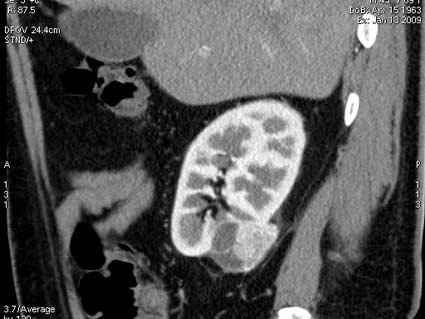

При КТ с контрастированием тканевой компонент активно накапливает контраст

se003.jpg (38.03 КБ) 1009 просмотров